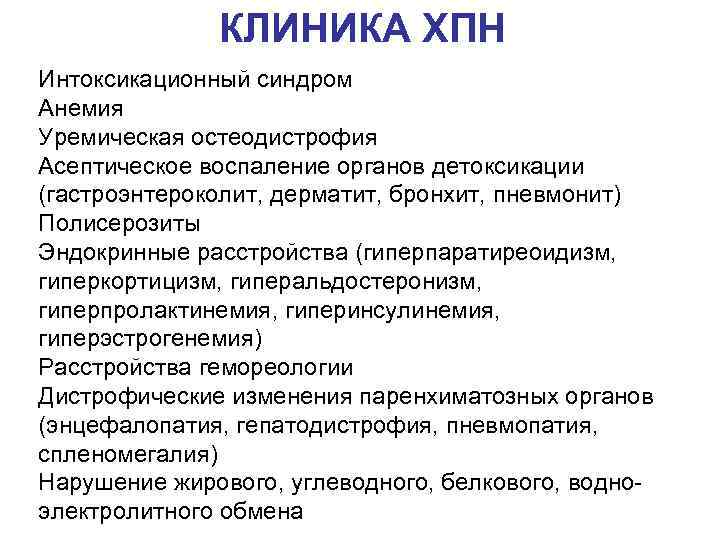

КЛИНИКА ХПН Интоксикационный синдром Анемия Уремическая остеодистрофия Асептическое воспаление органов детоксикации (гастроэнтероколит, дерматит, бронхит, пневмонит) Полисерозиты Эндокринные расстройства (гиперпаратиреоидизм, гиперкортицизм, гиперальдостеронизм, гиперпролактинемия, гиперинсулинемия, гиперэстрогенемия) Расстройства гемореологии Дистрофические изменения паренхиматозных органов (энцефалопатия, гепатодистрофия, пневмопатия, спленомегалия) Нарушение жирового, углеводного, белкового, водноэлектролитного обмена

КЛИНИКА ХПН Интоксикационный синдром Анемия Уремическая остеодистрофия Асептическое воспаление органов детоксикации (гастроэнтероколит, дерматит, бронхит, пневмонит) Полисерозиты Эндокринные расстройства (гиперпаратиреоидизм, гиперкортицизм, гиперальдостеронизм, гиперпролактинемия, гиперинсулинемия, гиперэстрогенемия) Расстройства гемореологии Дистрофические изменения паренхиматозных органов (энцефалопатия, гепатодистрофия, пневмопатия, спленомегалия) Нарушение жирового, углеводного, белкового, водноэлектролитного обмена